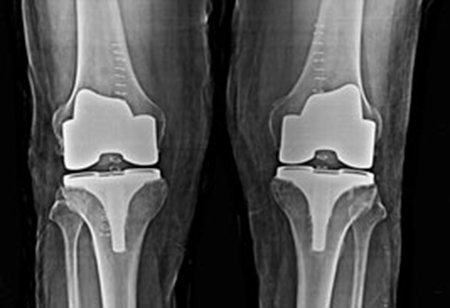

Total knee replacement surgery is a surgery in which the worn out or damaged surface of the knee joint is replaced with prosthetic artificial surface made up of special metals like chromium-cobalt, oxinium, titanium or polyethylene. The aim of this surgical procedure is to relieve you of your pain, deformity and swelling. So that you can get back to your active life. Now, that you have been suggested surgery, we help you plan and go for it.

Robotic knee replacement surgery is performed by the surgeon with the help of the robot. The surgeon will open up the knee, make a real time map of the deformed/ damaged surface ends of the bones and then using the robot plan the surgery. Once the surgery is virtually performed on the robotic screen, the robotic burrs are used to burr off/ shave off the surface and ligament balance is achieved throughout the range of movement, artificial implant is fitted on the surface. The wound is closed and dressing applied. You are then shifted to the recovery room!

Usually after discharge we call you after 8 days. If you have asked for a home dressing, we will help you with that and then your visit will be after one month from date of surgery, where we will HOPE to see you walk into the doctor’s office for an Xray and physical check of the knee. Fix up an appointment before coming for next visit.